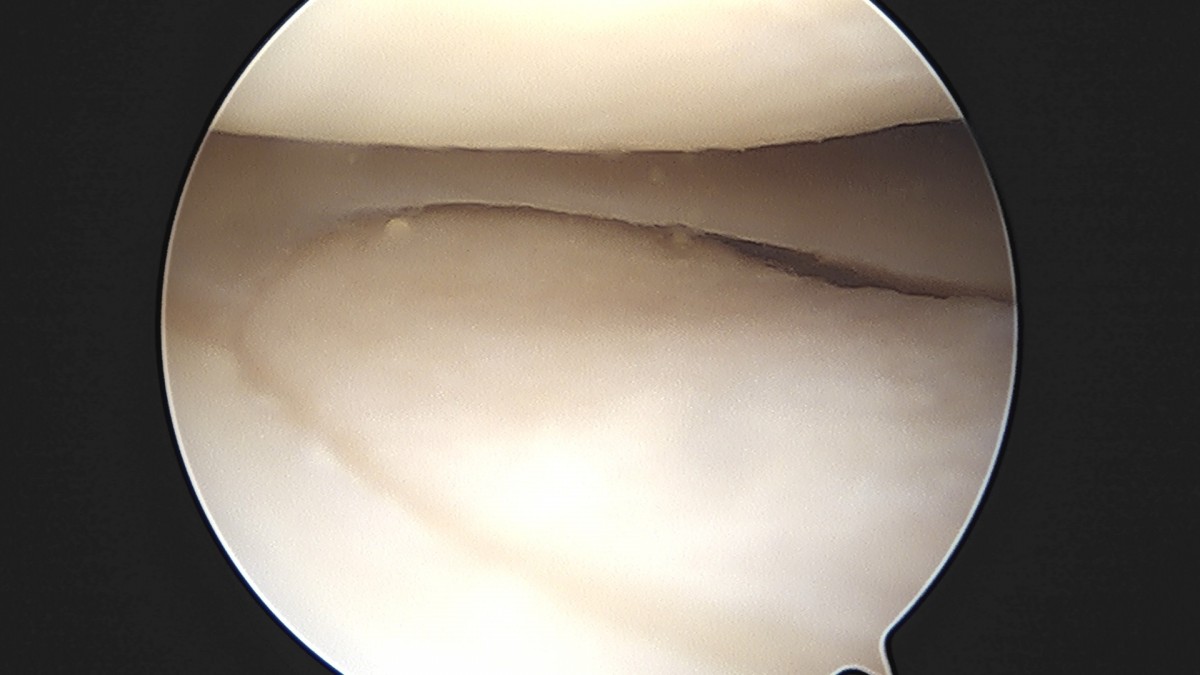

이재상원장님 무릎 반월상 연골판 절제술 고기O 환자

dae765e4d9ac96aee867c9d6292d8784_1758005093_4796.jpg